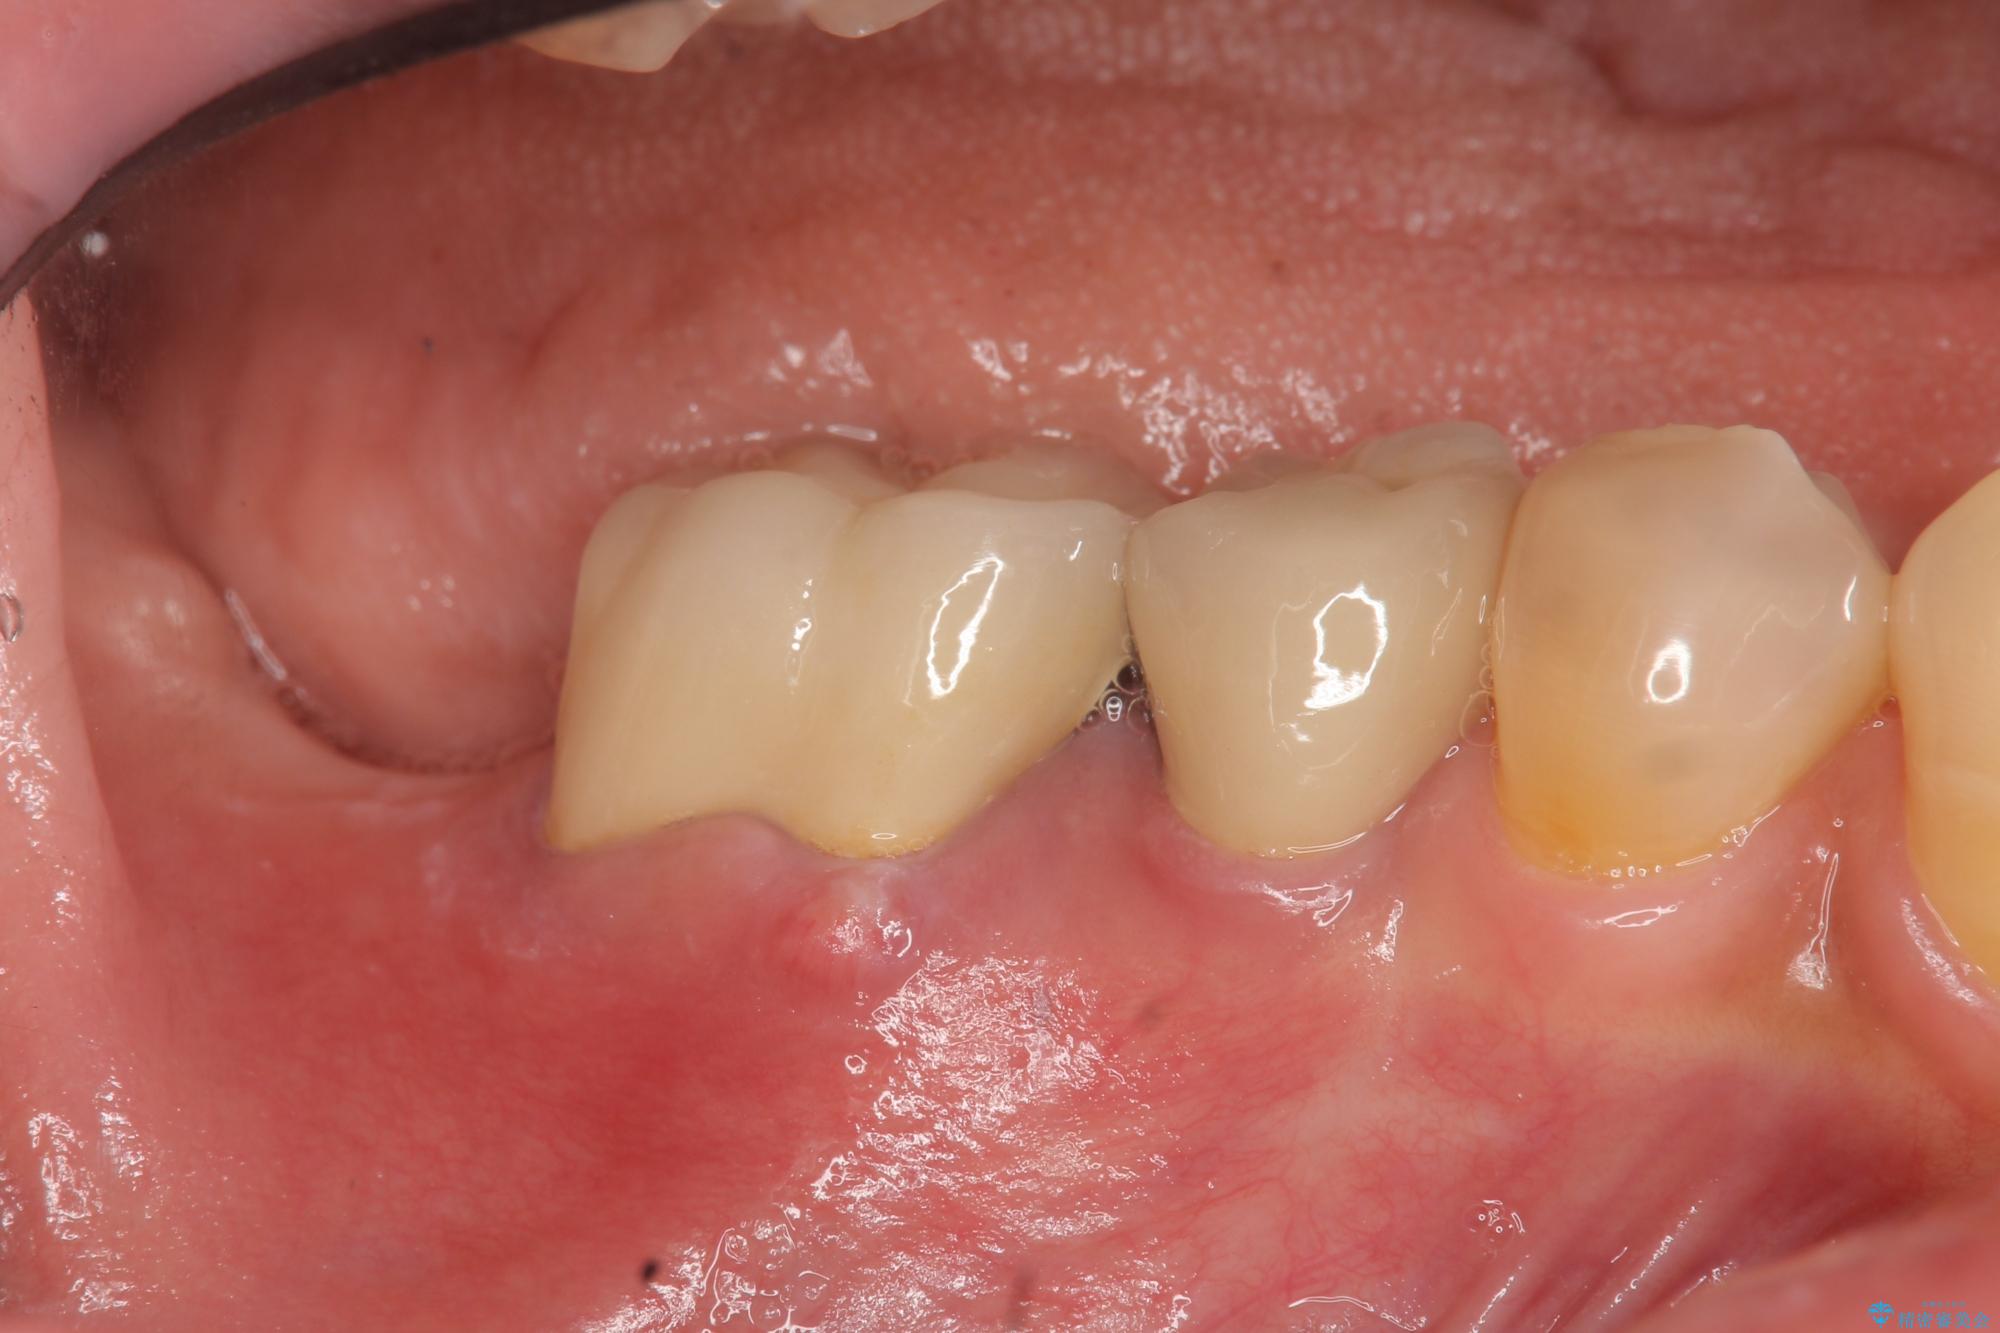

治療後

奥歯から膿のにおいがする インプラントによる機能回復 治療後画像 奥歯から膿のにおいがする インプラントによる機能回復 治療後画像 奥歯から膿のにおいがする インプラントによる機能回復 治療後画像 奥歯から膿のにおいがする インプラントによる機能回復 治療後画像